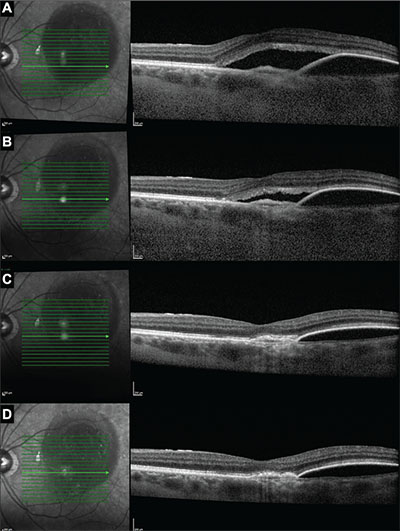

| Figure 4. Optical coherence tomography images in one subject at enrollment (A), week four (B), week eight (C) and week 12 (D) show improvement in subretinal fluid and pigment epithelial detachment after the addition of dorzolamide-timolol to the monthly aflibercept regimen. Prior to enrollment, this patient had received 16 aflibercept injections. |

In addition to the decrease in CST (Figure 2), mean maximum SRF height also decreased from 126.6 μm at enrollment to 49.5 μm at the final visit (P=0.02) with the decrease also noted at the first visit after enrollment (Figure 3). Moreover, all study eyes experienced a decrease in maximum SRF height at the final visit. Additionally, four out of the 10 study eyes demonstrated complete resolution of SRF by the final visit.

Ten patients (10 study eyes) completed the study protocol and were included for the final analysis. Mean CST decreased from 419.7 μm at enrollment to 334.1 μm at the final visit (P=0.01), with a decrease noted as soon as the first visit after enrollment. All patients were found to have a reduced CST on the final visit after instilling the combination therapy.